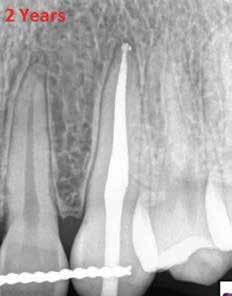

1. a-n. ábrák: Preoperatív CBCT-felvétel a bal alsó 6-os (3.6) fogról. Az axialis (a), coronalis (b) és sagittalis (c) nézeteken a mezialis és distalis gyökerek apicalis harmada körül sugáráteresztő zóna és ép buccalis corticalis csont látható. Egy olyan sablont terveztünk, amely jelezte a csontablak határait az apicalis terület pontos elérése érdekében (d). A mikrosebészeti bevatkozás során a sablont a helyére illesztettük (e), a csontablak határait megjelöltük (f) egy Piezotome CUBE LED kézi-darabba fogott fűrésszel, majd kivágtuk és eltávolítottuk (g és h) az apicalis területhez történő hozzáférés, illetve a mezialis és distalis gyökerek rezekciójának, retrográd preparációjának és retrográd gyökértömésének elvégzése érdekében (i). Végezetül a csontablakot visszaillesztettük és kollagén szivaccsal stabilizáltuk (j). A műtét után közvetlenül készített röntgenfelvétel a 3.6-os fogról (k). A kétéves kontroll során készített CBCT-felvétel: axialis (l), coronalis (m) és sagittalis (n) nézetek.

A beavatkozás során helyi érzéstelenítésben teljes vastagságú mucoperiostealis lebenyt képeztünk, és a sablon segítségével bejelöltük a preparálandó csontablak határait. Az ablak széleinek megfelelően Piezotome CUBE LED kézi-darabbal (ACTEON) a kortikális teljes vastagságában vágást ejtettünk, majd az így kapott csontlemezt (ablakot) eltávolítottuk (1. e–h. ábra), és ezt követően steril fiziológiás sóoldatba helyeztük. A rezekció elvégzését követően (1. i. ábra) a mezialis csatornákat ultrahangos eszközök segítségével (NSK) retrográd irányból preparáltuk, majd az így kialakított mélyedésbe retrográd gyökértömést készítettünk. A tömés anyagául az EndoSequence BC RRM Fast Set Putty-t (Brasseler) választottuk. A tömés elkészítését követően a csontablakot visszaillesztettük, és a stabilizálása érdekében a vágásoknak megfelelően kialakult résekbe kollagén szivacsokat (Collagen Tape, Zimmer Biomet) helyeztünk (1. j-k. ábra). A lebenyt 6/0-s Prolene varratokkal (Corpaul) rögzítettük.

A kétéves kontroll során elvégzett klinikai és radiológiai vizsgálat (CBCT-felvétel) a periapicalis elváltozások megszűnését és a corticalis csontállomány tünet- és szövődménymentes gyógyulását